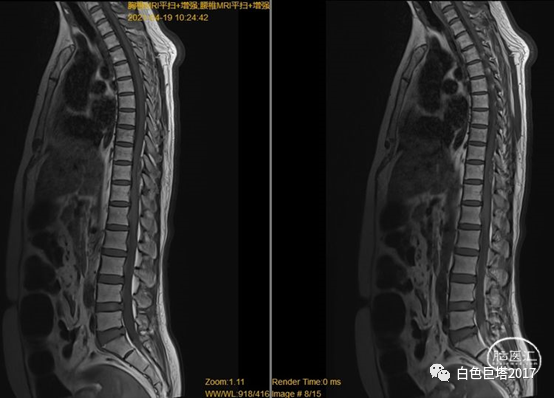

考虑患者体格检查结果与既往病史不符合,患者语言功能障碍,不能很好配合检查。请我科会诊,急诊完善胸腰椎磁共振平扫+增强。

图示:T1

图示:T2,红色箭头所示T10-T12水平椎管内硬脊膜外低信号。

图示:T2压脂像,T8椎体血管瘤。

T2水平面可见相应节段脊髓明显受压。

诊断考虑1.硬脊膜外血肿(T10-12),2.症状性癫痫,3.脑出血后遗症,4.高血压3级 很高危,5.2型糖尿病,6.T8椎体血管瘤,7.右肱骨外科颈骨折固定术后,8.左肾结石,9.肝内胆管结石,10.腰椎退行性病变。

患者无外伤病史,病因可能为椎管内血管畸形如硬脊膜动静脉瘘或海绵状血管畸形,立即急诊手术挽救患者神经功能。